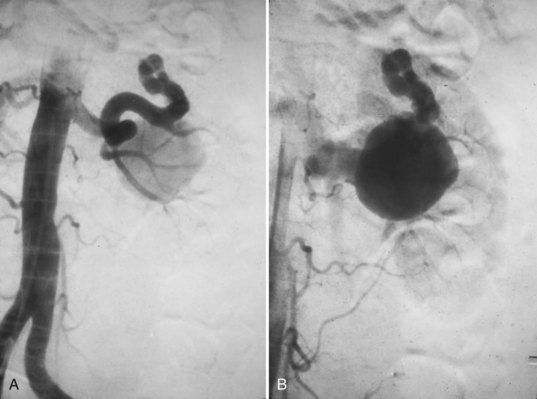

Aneurysmal disease can lead to progressive renal damage and hypertension. By definition these lesions may be true (congenital or acquired) or false from trauma. Angiographically they can be divided into saccular, dissecting, fusiform, and intrarenal. Saccular forms occur in the main renal artery or at the anterior-posterior branch point and are the most common (Fig. 54–45). Dissecting aneurysms result from a disruption of the internal elastic membrane in certain populations (e.g., atherosclerosis, intimal fibrodysplasia, and perimedial fibrodysplasia). Fusiform aneurysms are noncalcified and common in younger hypertensive patients with fibromuscular dysplasia (Fig. 54–46).

Figure 54–45 Saccular aneurysm in left renal artery (atherosclerosis).

(From Libertino JA. Reconstructive urologic surgery. 3rd ed. Philadelphia: Mosby; 1997.)

Figure 54–46 Fusiform aneurysms in right renal artery.

Intrarenal aneurysms are considered congenital and account for one fifth of aneurysmal disease affecting the kidney (Fig. 54–47). In some instances they may develop secondary to atherosclerosis, mural dysplasia, trauma, inflammation (arteritis), or needle biopsy. Intervention is warranted for lesions larger than 2 cm or those associated with hypertension. Lesions can rupture and dissect leading to ischemia or may contribute to thrombus formation and warrant intervention (revascularization or coil placement). Women in childbearing age with evidence of aneurysms are urged to undergo repair secondary to risk of rupture and associated high rates of maternal and fetal mortality (Figs. 54-48 and 54-49) (Yang and Hye, 1996; Centenera et al, 1998).

Figure 54–47 A, Large left congenital renal aneurysm and arteriovenous malformation. B, Note early filling of the renal vein and inferior vena cava.